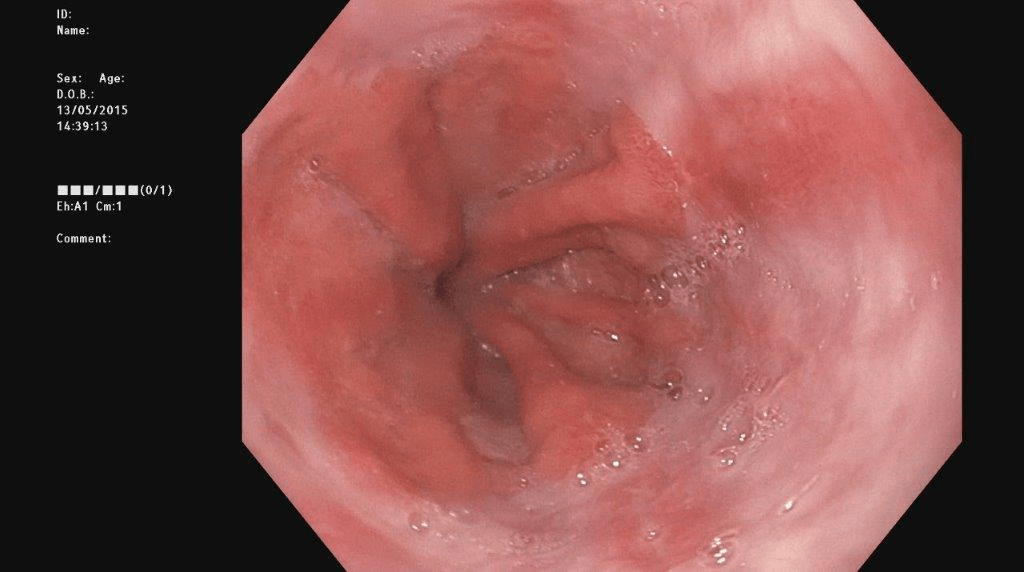

Refer to caption

(a) No abnormality

(b) Polyp

(c) Oesophagitis

(d) Ulcerative Colitis

Figure 1: Illustrations of question-answer pairs along with common abnormalities in gastrointestinal image from ImageCLEFmed-MEDVQA-GI-2023 dataset

The new dataset released for the ImageCLEFmed-MEDVQA-GI-2023 challenge is based on the HyperKvasir dataset [29], the largest gastrointestinal collections with more than 100,000 images, with the additional question-and-answer ground truth developed by medical collaborators. The development set and test set include a total of 3949 images from different procedures such as gastroscopy and colonoscopy, spanning the entire gastrointestinal tract, from mouth to anus. Each image has a total of 18 questions about abnormalities, surgical instruments, normal findings and other artefacts, with multiple answers possible for each, as shown in Table 1. Not all questions will be relevant to the provided image, and the VQA system should be able to handle cases where there is no correct answer. Figure 1 depicts several examples of question-answer pairs on common abnormalities in gastrointestinal tract, such as Colon Polyps, Oesophagitis, and Ulcerative Colitis. As shown in Figure 1(d), there are three possible answers to the question "What color is the abnormality?": "Pink," "Red," and "White", and a typical VQA system should be able to identify all three colors. In general, the image may contains a variety of noise and components that locates across abnormalities, such as highlight spots or instruments, which pose a significant challenge in developing efficient VQA systems for gastrointestinal domain.